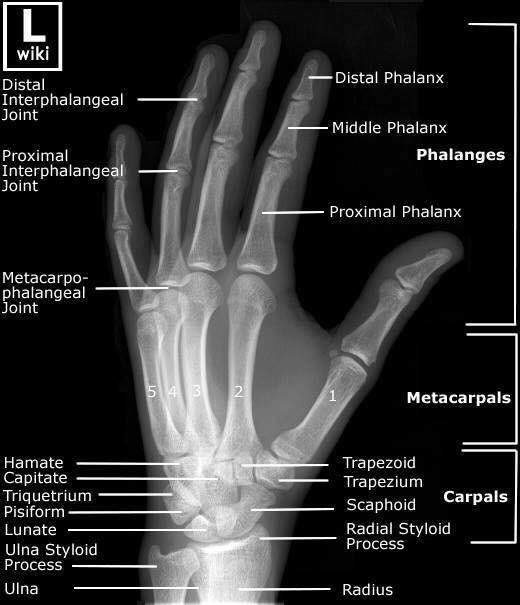

Las radiografías, generalmente llamadas rayos X, producen imágenes como sombras de huesos y ciertos órganos y tejidos. Las radiografías son muy buenas para detectar problemas óseos. Pueden mostrar algunos órganos y tejidos blandos; sin embargo, la MRI y la CT suelen crear mejores imágenes de los mismos. Aun así, las radiografías son rápidas, fáciles de obtener y menos costosas que los otros estudios, por lo que se pueden usar para obtener información rápidamente.

Un tubo especial dentro de la máquina de rayos X emite un haz de radiación controlada. Los tejidos del cuerpo absorben o bloquean la radiación en diferentes grados. Los tejidos densos como los huesos bloquean la mayor parte de la radiación, pero los tejidos blandos, como la grasa o los músculos, bloquean menos radiación. Después de pasar por el cuerpo, el haz alcanza una pieza de un fragmento de película o un detector especial. Los tejidos que bloquean altas cantidades de radiación, como los huesos, aparecen como áreas blancas en un fondo negro. Los tejidos blandos bloquean menos radiación y aparecen en tonos de gris. Los órganos que contienen principalmente aire (como los pulmones) aparecen en negro. Los tumores son por lo general más densos que el tejido que los rodea, por lo que suelen verse en tonos grises más claros.